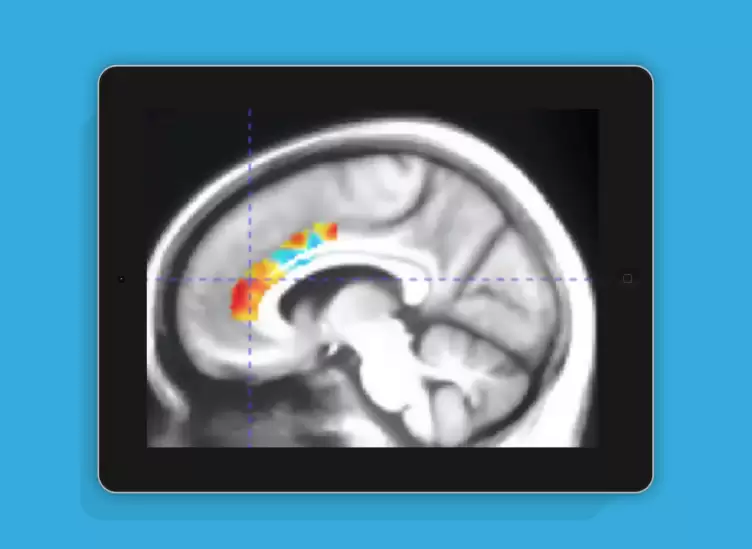

这项研究由Mouna Attarha领衔的团队完成,重点关注计算机化认知训练对健康老年群体脑神经功能的影响。通过使用[18F]Fluoroethoxybenzovesamicol正电子发射断层扫描技术,研究人员观察了参与者大脑中囊泡乙酰胆碱转运蛋白水平的变化,旨在评估认知训练对神经可塑性的促进作用。研究采用随机对照临床试验的形式展开,项目名称为"通过神经可塑性基础计算机化训练改善老年神经系统健康"(INHANCE),相关成果已正式发表。